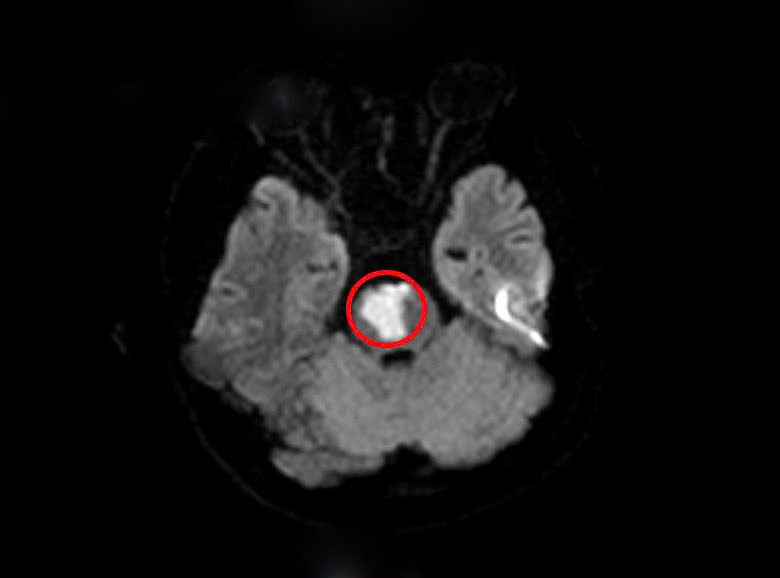

Kết quả chụp MRI sọ não bệnh nhân phát hiện khối nhồi máu tiểu não, cầu não do tắc động mạch thân nền. Xét nghiệm máu có rối loạn lipid máu, một yếu tố nguy cơ dẫn đến các vấn đề tim mạch và mạch máu não. Người bệnh được phát hiện bất thường trong hệ gene làm tăng nguy cơ tạo huyết khối tắc mạch.

Kết quả chụp não phát hiện nhồi máu não. Ảnh: Bệnh viện cung cấp